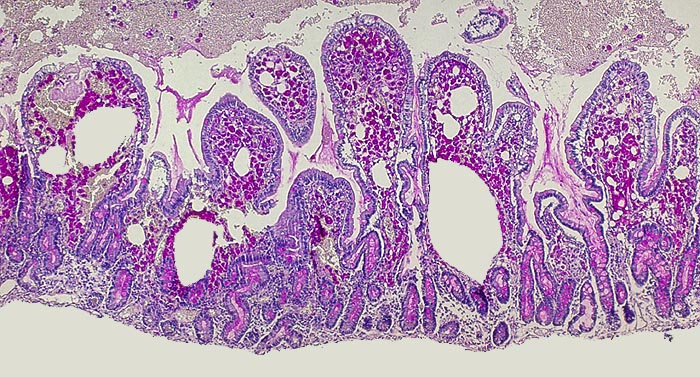

AP/ Morbus Whipple

Morbus Whipple

Dünndarm

Pathologischer Befund